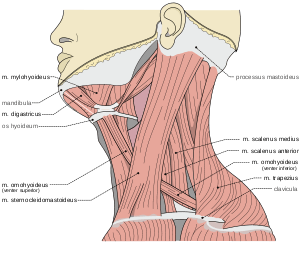

Musculi coli base

Musculi coli base- Scalene muscles. Muscles of the neck. Lateral view.

- Scalene muscles. Muscles of the neck. Lateral view.